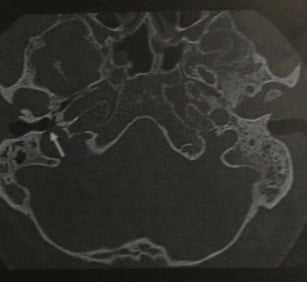

- Мягкотканная структур» без костного покрытия, выступающая в полость среднего уха.

- При выполнении исследования с контрастированием контуры луковицы характеризуются дольчатостью или вытянутостью при сосудистой мальформации

- Вытянутость яремной луковицы в латеральном и верхнем направлении, в полость среднего уха, по данным МРВ.

Типичная картина дегисценции яремной луковицы: